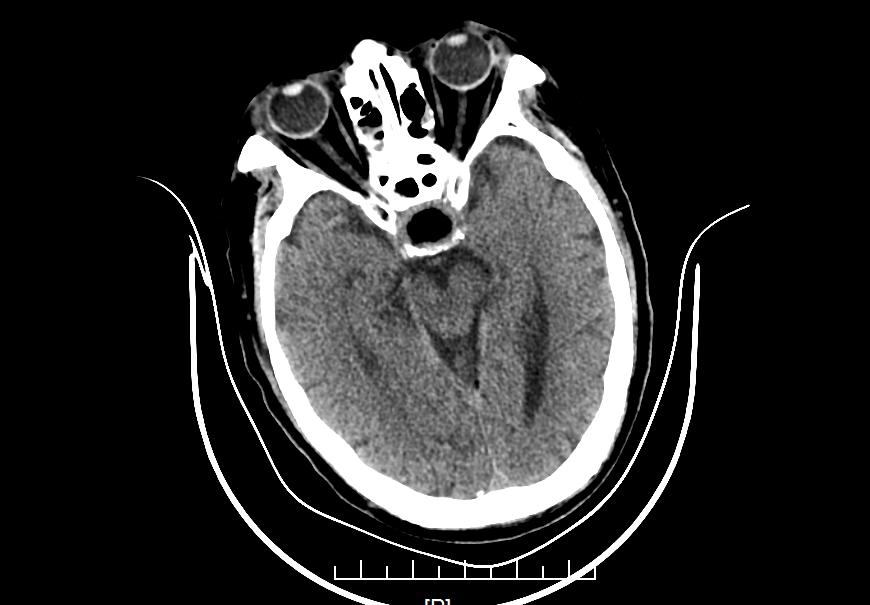

术后复查CT结果如下所示:

术后CT